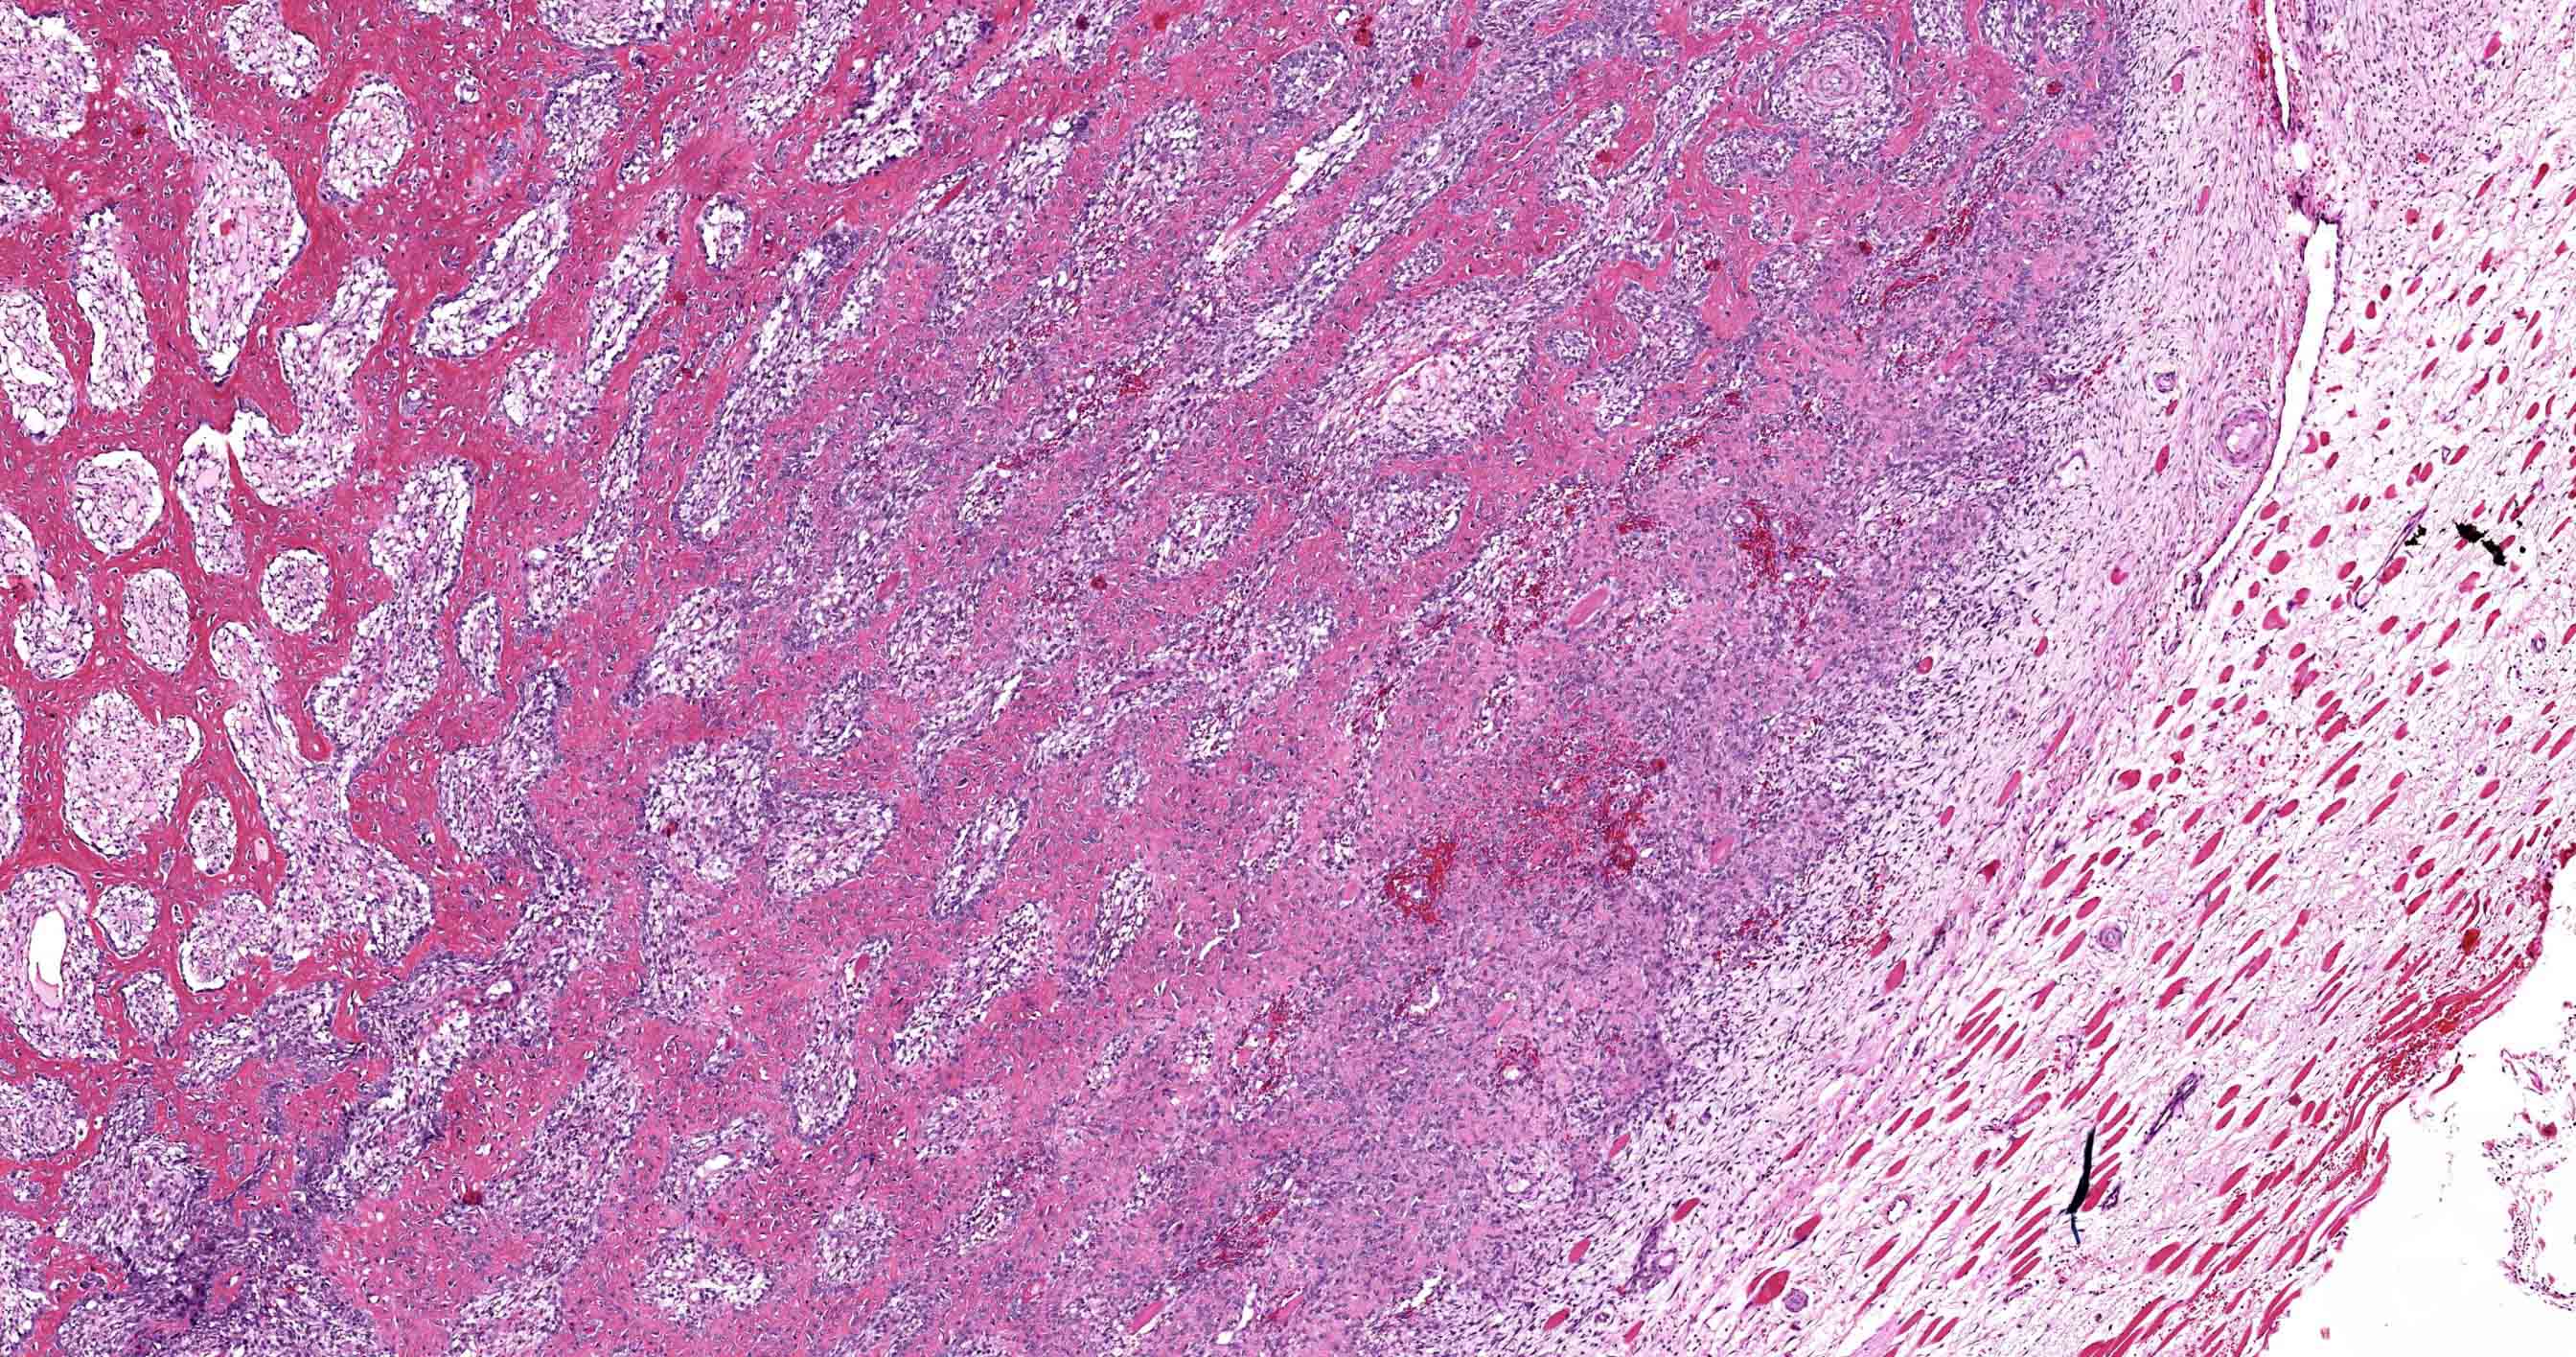

- Histologically, zonal pattern is characteristic with different degrees of cellular differentiation (inner zone, intermediate zone and peripheral zone)

- Inner central zone:

- Composed of fibroblastic / myofibroblastic proliferation, which is richly vascular, rich in inflammatory cells and resembles nodular fasciitis; some multinucleated giant cells may also be seen

- Intermediate zone:

- There is a mixture of fibroblasts and osteoblasts along with erratic osteoid separated by small sized vessels

- Peripheral zone:

- Osteoid undergoes calcification and leads to lamellar bone formation

- Extreme periphery / margin shows mature bone with osteoblastic rimming and little to no pleomorphism

- Lesion is separated from the normal tissue (muscle) by a zone of loose, myxoid fibrous tissue

- Intermediate stage (4 - 8 weeks):

- Zonal pattern is appreciated with central zone, intermediate zone and peripheral zone

Microscopic (histologic) images

- Comment: The sections from the mass show a circumscribed lesion with characteristic zonal pattern, with inner zone showing tissue culture-like background, against which are seen plump fibroblasts and myofibroblasts. This area is rimmed by immature bone in the middle and mature lamellar bone at the periphery.